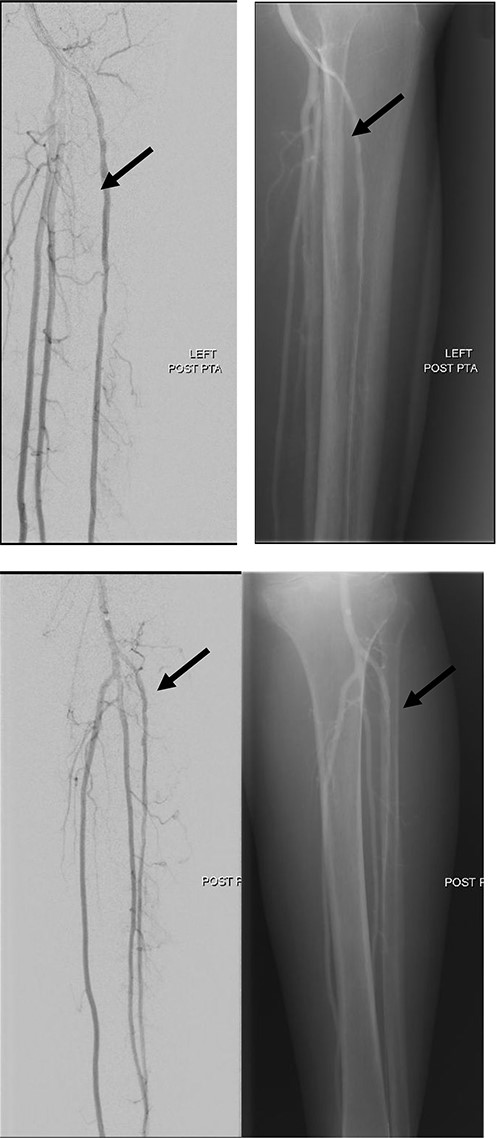

She subsequently underwent left lower limb angioplasty and stenting of the ATA with good results (Figs 4–7) and was started on antiplatelet therapy. Following successful angioplasty, she underwent early wound coverage procedure. A medially based rotation advancement flap was raised for coverage of wound defect. Patient completed 2 weeks course of broad-spectrum antibiotics post-operatively. Patient’s flap was stable and she was allowed partial weight bear over her left lower limb with Darco shoes at post-operative Day 12.

Good arterial flow of the ATA (arrow) after successful angioplasty and stenting.

Arterial flow noted at distal ATA and dorsalis pedis artery (arrow) after successful angioplasty and stenting.